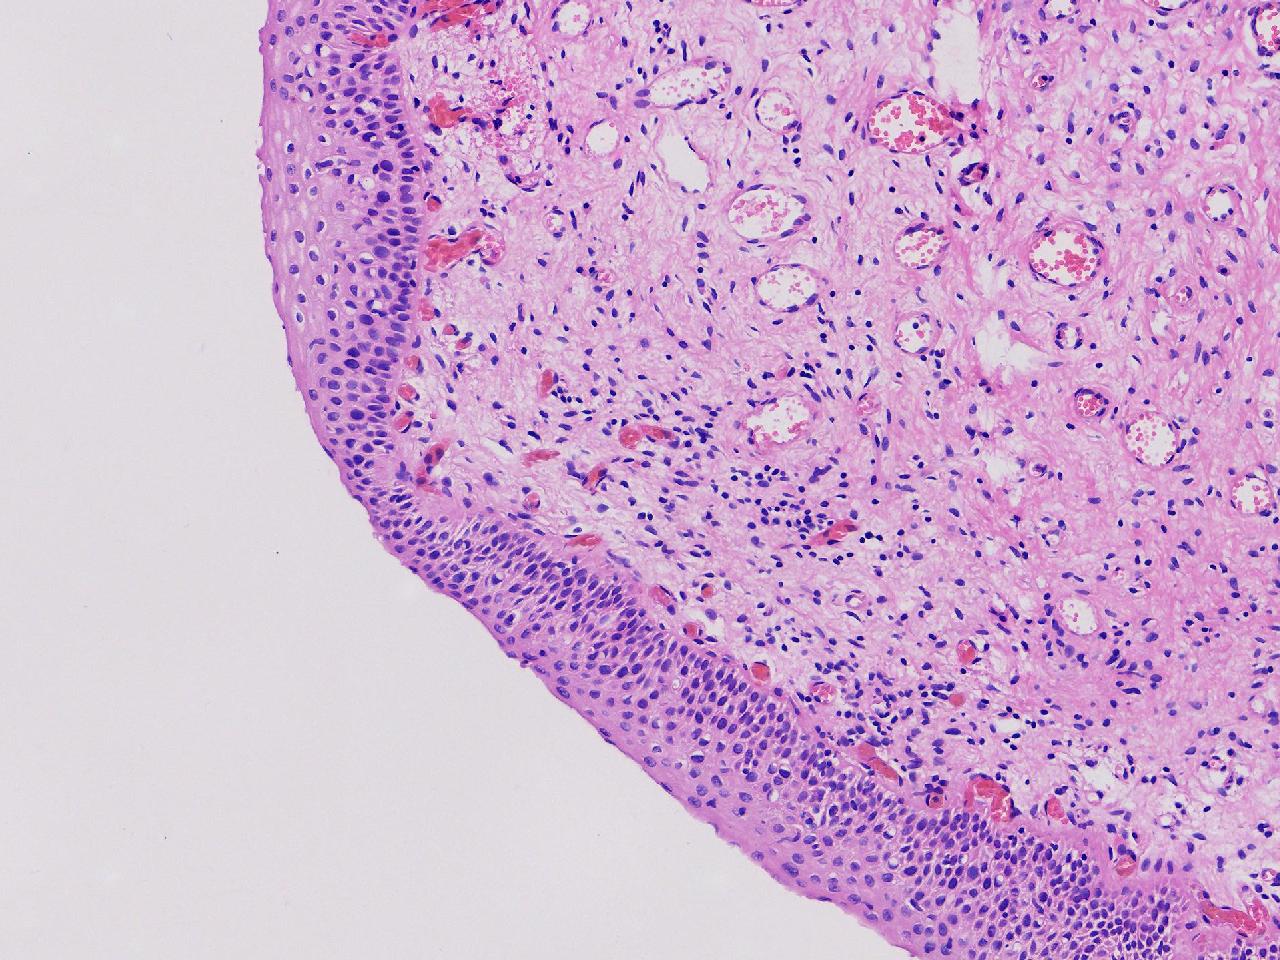

CIN1级? CIN2级?

性别年龄61岁临床诊断

一般病史女,61岁,宫颈活检,,HPV6+ 52+

标本名称宫颈活检

大体所见灰白色不整形软组织1块,直径0.3厘米。

CIN2倒是不够,图3有几个像挖空细胞,HPV有阳,勉强可以考虑小灶LSIL。

• zhuang xia nan:  是的。  2级肯定不够,有挖空细胞,小灶1级。    谢谢老师指点。

CIN1.